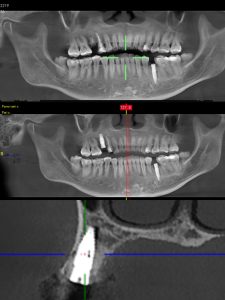

·數字化種植導航技術縮短手術时間

·配合朗視CBCT實現精準三維建

·適配ALL-ON-4等複雜術式

亞洲人種植導航系统